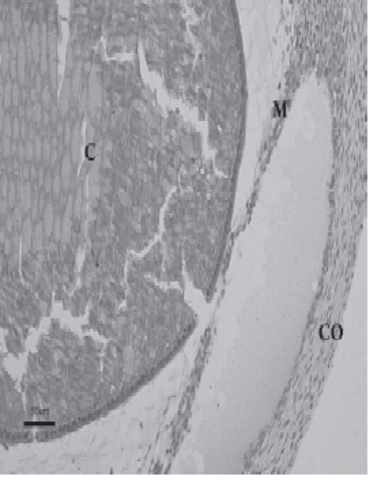

La placoda cristaliniana se invagina, hasta que un día más tarde se desprende de la superficie ectodérmica, formando la vesícula cristaliniana. Inicialmente ésta presenta una cavidad en su interior. Este fenómeno coincide con la aparición del cuerpo vítreo primario, entre la vesícula y la cúpula óptica Las fibras de la pared profunda de la vesícula cristaliniana se diferencian para formar las fibras primarias del cristalino. De esta forma, se va obliterando lacavidad de la vesícula cristaliniana

• Desarrollo del cristalino

La vesícula del cristalino recibe irrigación de la arteria hialoidea, que también irriga a la retina en desarrollo. Cuando el cristalino madura en la vida fetal, la porción de la arteria hialoidea que cruza el cuerpo vítreo degenera, dando lugar en el adulto al ligamento de CloquetStilling, que se dispone desde la cara posterior del cristalino hasta la papila. La porción proximal de la arteria hialoidease convierte en la arteria central de la retina.